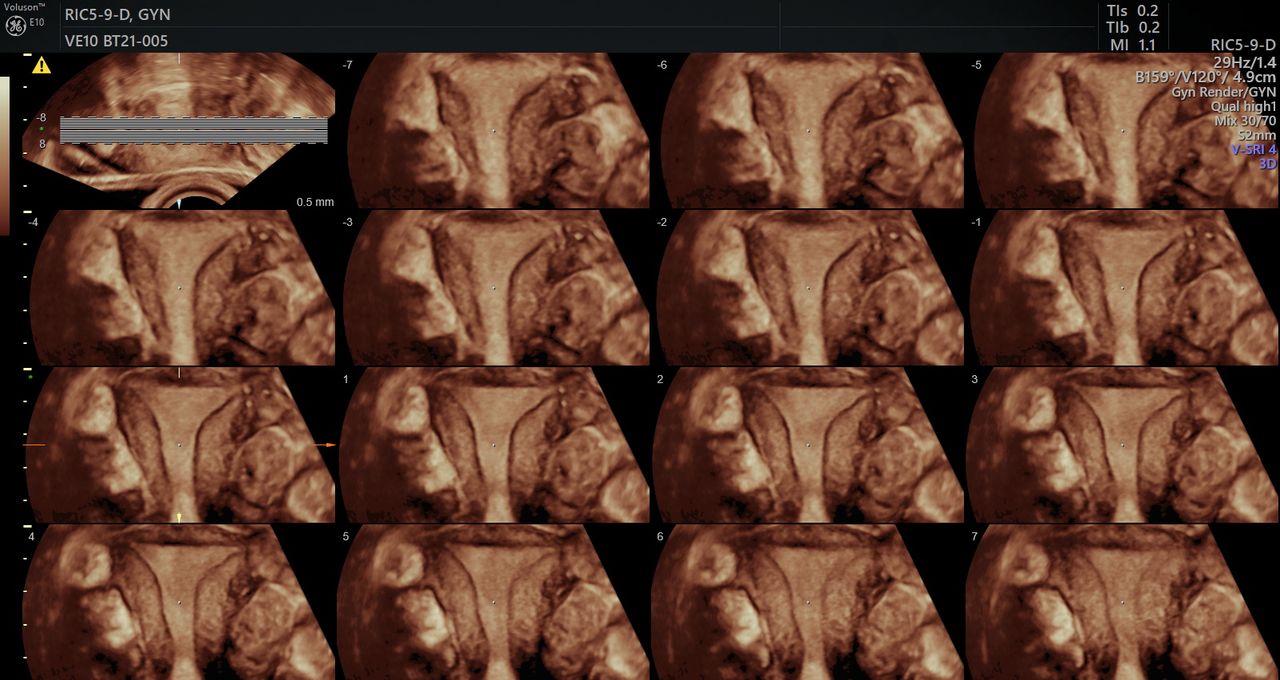

Durante gli studi in medicina sento che la mia vocazione è la ginecologia, un’affascinante specialità tutta incentrata sulla donna che mi ha permesso di studiare la patologia ginecologica e oncologica (in particolare di perfezionarmi come ultraspecialista in diagnostica ecografica ginecologica ed ostetrica di 2 livello).

Ho raffinato negli anni di studio le mie conoscenze per poter fare diagnosi complesse in ambito sia ginecologico che ostetrico dove ho perseguito il sogno di far nascere i bambini e ancor prima di poterli guardare in pancia e aiutare le donne nel loro percorso per la vita a diventare madri…

Foto e video